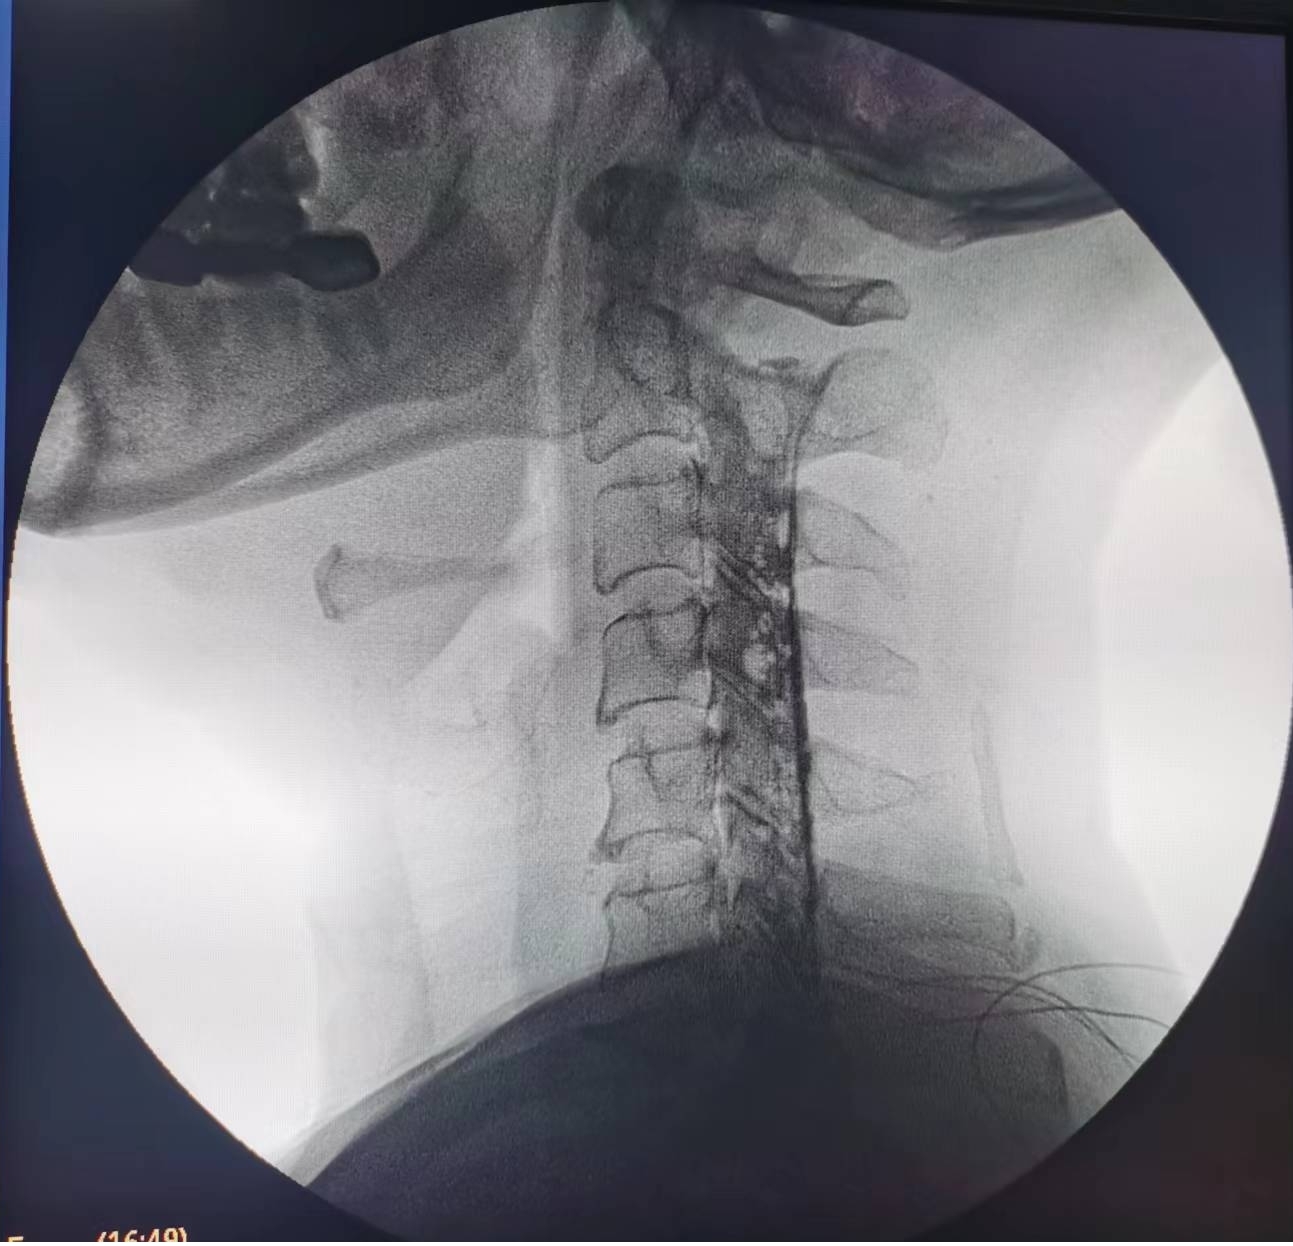

辗转来到泸州市中医医院疼痛科治疗。由于疼痛严重,外加严重缺乏睡眠,黄大伯入院时焦虑、精神状态很差。看着他急切想解除痛苦的眼神,疼痛科医生团队抓紧时间完善诊查,发现黄大伯病情为第6、7节颈椎间盘突出重,压迫左侧第7颈神经根导致。考虑他年龄较大,团队决定给他做一种微创手术——胶原酶化学溶解术:通过一支细小的针穿刺到突出的椎间盘,注射胶原酶,将突出的椎间盘溶解掉,以减除神经的压迫。

手术之后3天,黄大伯疼痛得到很好缓解,露出了许久没有的笑容,终于可以安心躺着睡觉了,1个月后基本恢复了正常生活,6个月后复查CT发现突出的颈椎间盘已经基本消失了,黄大伯一家人对治疗效果非常满意。

手术之前CT,巨大突出物 术后6个月复查CT:突出物消失